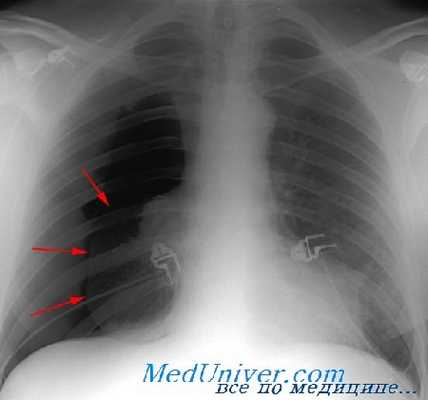

Отломки ребер могут повреждать не только легкое и плевру, но и межреберные сосуды, вследствие чего возникает внутреннее кровотечение в плевральную полость и формируется гемоторакс. Если острый конец ребра протыкает легкое, воздух выходит в плевральную полость, и образуется пневмоторакс.

О переломе ребер свидетельствует резкая боль в месте повреждения и боль при сдавлении грудной клетки в переднезаднем направлении. Дыхание становится поверхностным. Пациенту легче находиться в сидячем, чем в лежачем положении. Основным методом инструментальной диагностики является рентгенография ребер. Лечение заключается в устранении болей, профилактике пневмонии и облегчении дыхания.

Специфические лабораторные изменения при пневмотораксе не определяются. Окончательное подтверждение диагноза происходит после проведения рентгенологического исследования. При рентгенографии легких на стороне пневмоторакса определяется зона просветления, лишенная легочного рисунка на периферии и отделенная четкой границей от спавшегося легкого; смещение органов средостения в здоровую сторону, а купола диафрагмы книзу. При поведении диагностической плевральной пункции получается воздух, давление в полости плевры колеблется в пределах нуля.